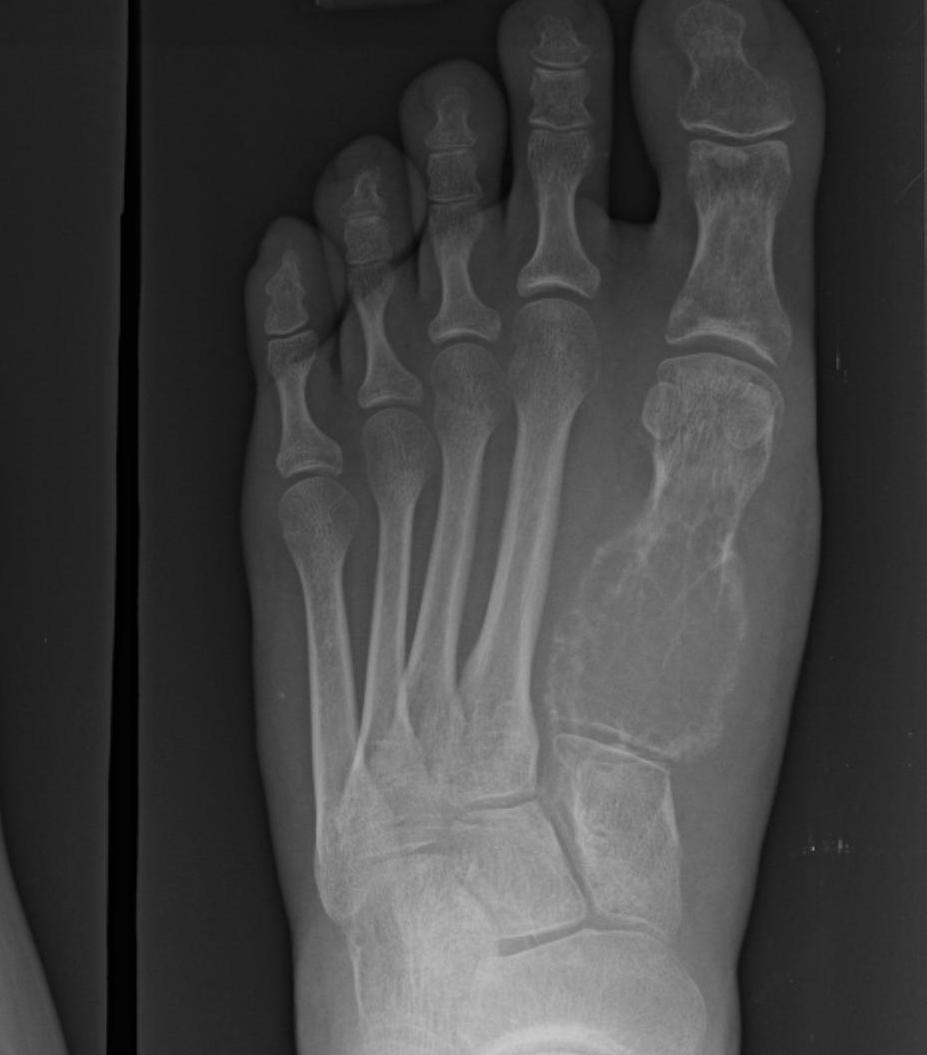

Foot

| Navicular / Medial cuneiform | Direct medial |

| Cuboid | Direct lateral |

| Intermediate cuneiform |

Between EHL and EDC Away from dorsalis pedis |

| Lateral cuneiform | Lateral to EDC |

| Metatarsals / phalangeals | Dorsal approach |

| Soft tissue tumour | Medial or lateral as required |